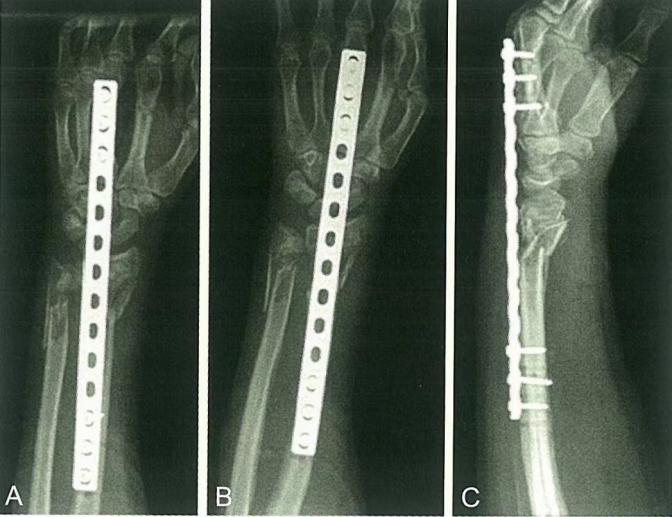

Primer ②